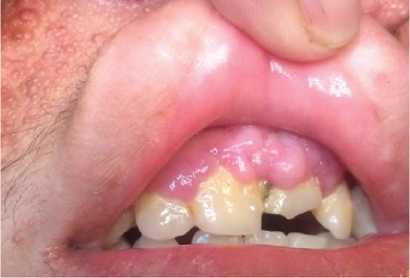

Al examen físico se observa pápulas eritematosas de diferentes tamaños distribuidas en el rostro (en las regiones de la frente, mentoniana, maseteriana, nasal y geniana) (Figura 1, A y B), en la parte endobucal se observó lesiones nodulares correspondiente a fibroma de mucosa gingival y lesiones del esmalte dental (Figura 2) a nivel de la encía superior; lesiones maculo-papulares hipocrómicas en región lumbar y fibromas periungueales (Figura 3).

A: Angiofibromas en región nasogeniana. B: Angiofibromas en región mentoniana.

Dentro de las manifestaciones dermatológicas; las máculas hipomelanoticas son prevalentes hasta en el 90% de niños menores de 5 años, pudiendo ser los primeros signos visibles de la enfermedad, además de los angiofibromas que también son comunes; la prevalencia aumenta con la edad y las lesiones progresan haciendo el componente fibroso más prominente. Los fibromas ungueales son menos comunes, generalmente aparecen en la adolescencia o en la edad adulta temprana, están ubicadas alrededor o debajo de las uñas; los parches de Shagreen son un criterio mayor dermatológico para el diagnóstico del complejo de esclerosis tuberosa y aparecen por lo general en la primera década de la vida inicialmente en la parte baja de la espalda; los fibromas gingivales son un criterio menor y se pueden incluir fibromas en cualquier sitio intraoral.1,2,8,9.

En base a ellos, el paciente presento como criterios mayores, angiofibromas faciales, fibromas ungueales, parche de Shagreen, nódulos subependimarios y como criterios menores los fibromas gingivales y los quistes renales, teniendo como resultado un diagnóstico definitivo del complejo de esclerosis tuberosa.